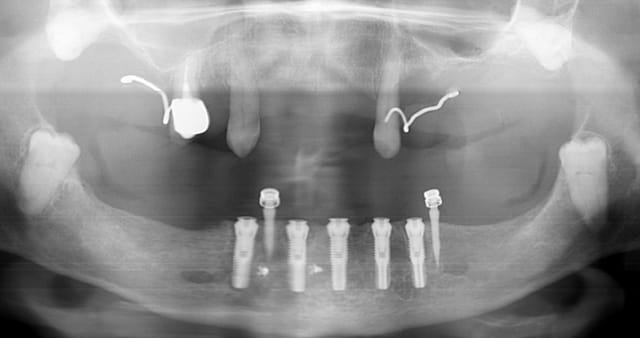

la pano post op

j'avais prévu de faire une MCI mais le manque de stabilité primaire des 2 implants côté droit m'en a dissuadé.

membrane biomend extend stabilisée par 2 petites vis de 4 mm de long de chez esasy implant. Os autogène et un peu de bio-os mélangé pour combler le defect.

les minis implants sont des intra-lock de 13 mm: http://intra-lock.com/index.php?option=com_virtuemart&page=shop.browse&category_id=96&Itemid=49 vendu chez orimplants

je vais les retirer dans au moins 4 mois, le jour de la pose de la prothèse finale.